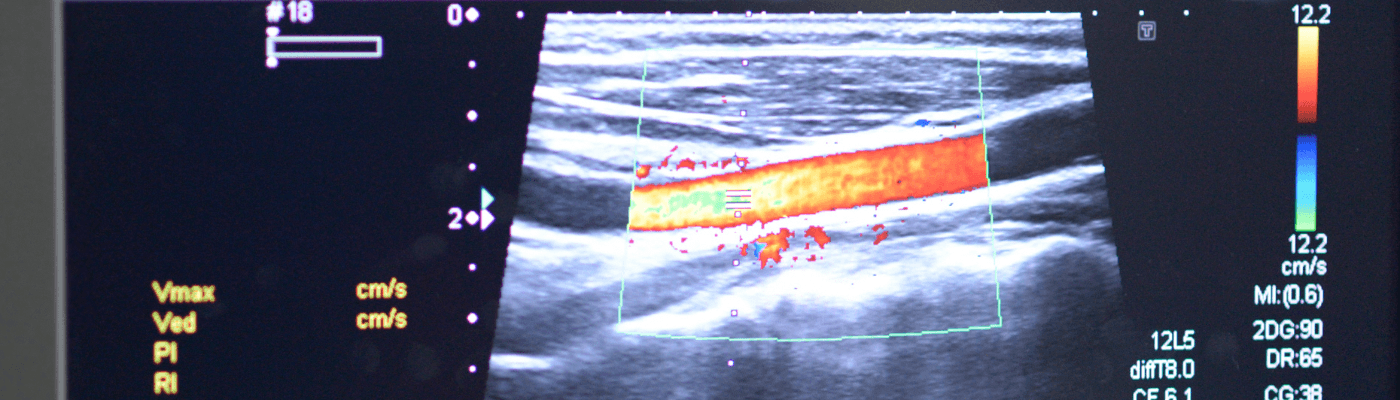

במכון האולטרסאונד באסותא אשדוד כלניות מבוצעות בדיקות דופלר לכלי דם על ידי צוות טכנאי אולטרסאונד מיומן. הבדיקות מפוענחות על ידי רופאים בכירים מומחים בתחום.